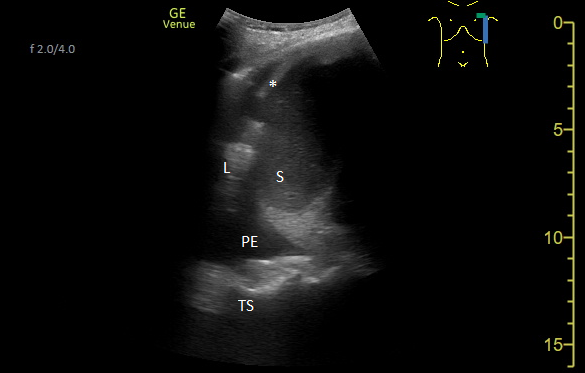

Une échographie pleuro-pulmonaire ciblée est effectuée. On visualise cette image en région thoracique latéro-postéro-basale gauche :